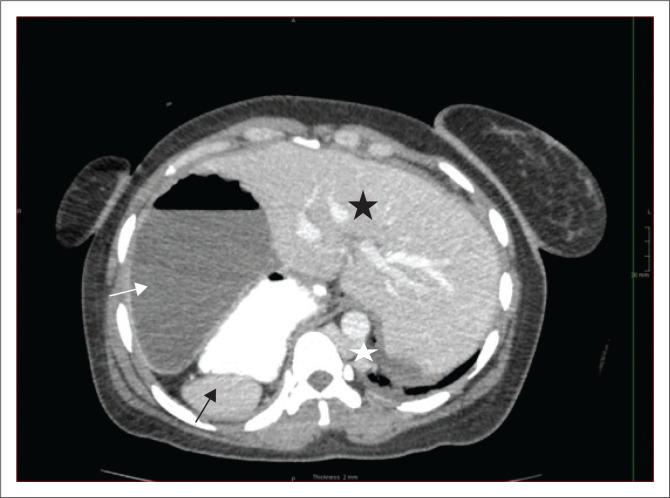

Heterotaxy syndrome, also known as situs ambiguous, is a spectrum of pathology due to loss of the normal right-to-left asymmetry of the thoraco-abdominal organs. This report describes the case of a 39-year-old female, previously well, who presented with bowel obstruction. CT showed features of left isomerism, with malrotation and volvulus.

Contribution: Heterotaxy syndrome consists of cardiac and non-cardiac manifestations. Imaging studies play a crucial role in the individualised management of the patient.